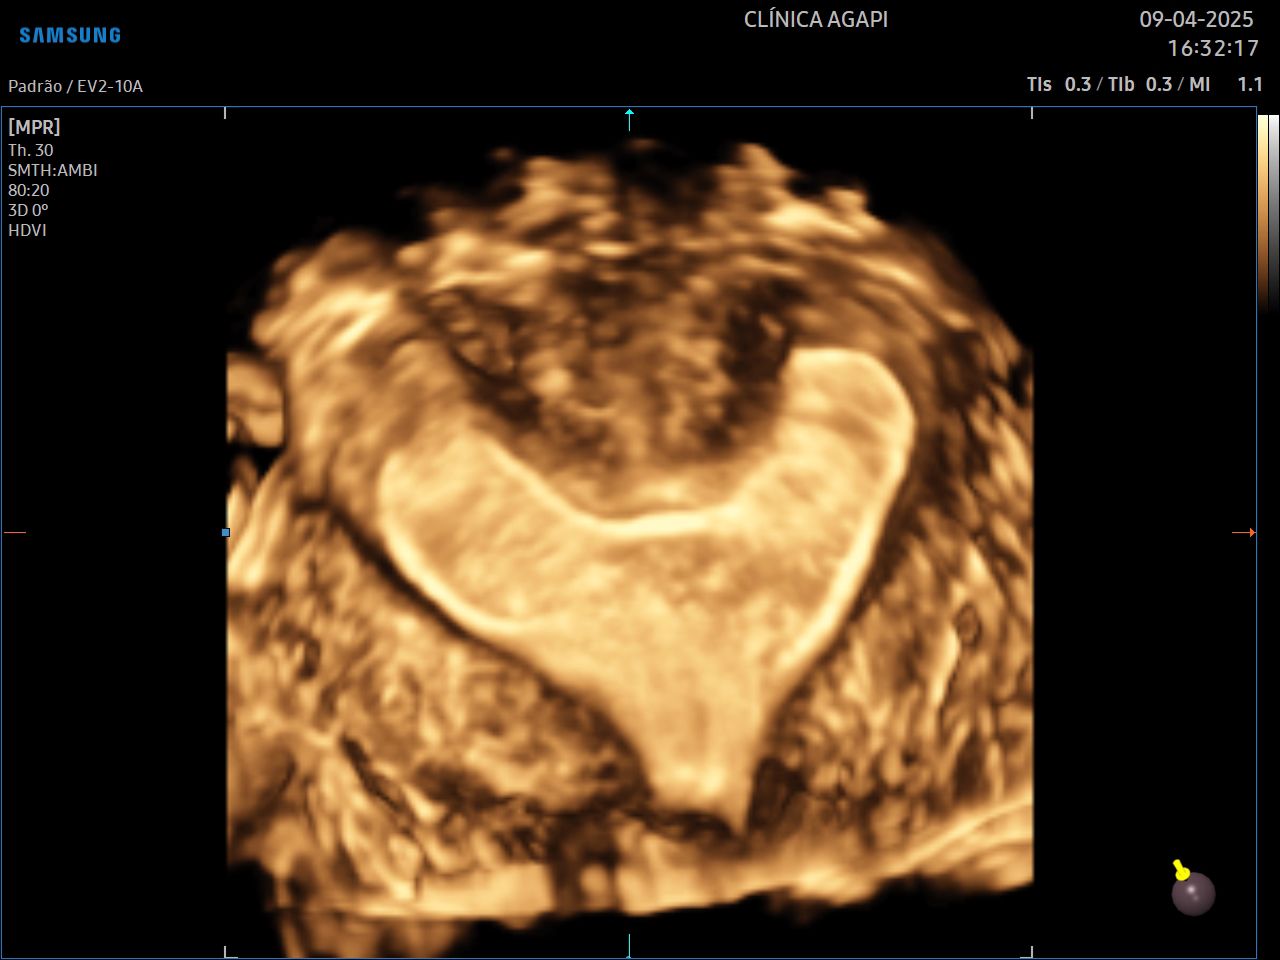

Ultrassonografia Ginecológica 3D/4D

Exame complementar à ultrassonografia transvaginal comum, que auxilia no diagnóstico de algumas malformações uterinas.